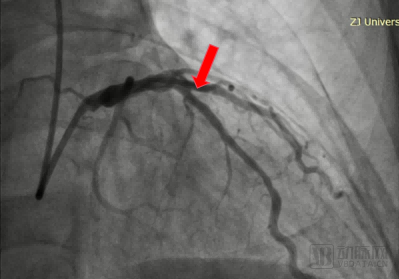

During the surgery, Academician Wang Jian'an's team first used a 3.0 × 13mm spinous process balloon to pre dilate the diseased blood vessel. Subsequently, a 3.5 × 15mm rectangular coronary artery remodeling catheter was used to dilate the blood vessels at 10atm and initiate laser therapy. Postoperative imaging showed good dilation effect, no residual stenosis or dissection, TIMI blood flow level 3, and the surgery was successfully completed.

Guide wire passes through the patient's lesion site